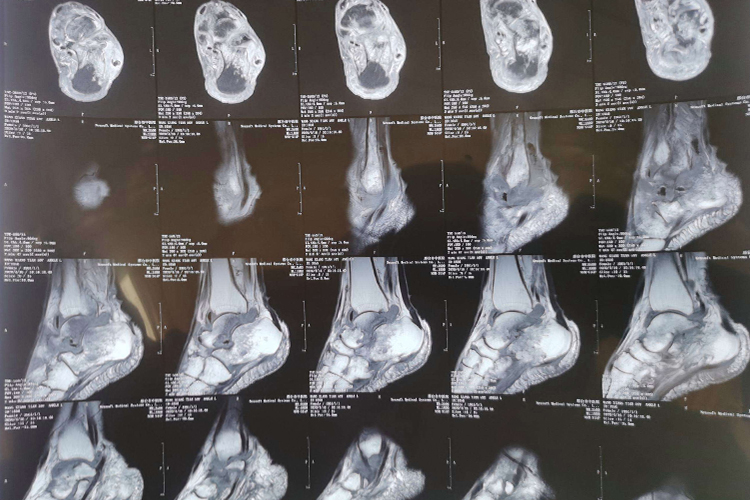

核磁共振是一项常用的检查手段,正常的脚踝进行核磁共振检查,可以观察骨骼、肌肉、韧带、关节囊等部位。

在核磁共振检查中,正常脚踝可表现为:

关节骨端:表现为在不同加权图像上呈一薄层清晰锐利的低信号影。

关节间隙:关节间隙有少量滑液,滑液在SET1WI上呈薄层低信号,在T2WI上呈细条状高信号。

关节囊、韧带、关节盘:在MRI各序列上均呈光滑连续的小弧形线样低信号,韧带在核磁共振上表现为条状低信号影。

异常表现

踝关节损伤容易导致外侧副韧带损伤,最先受到应力并且受力最大,也最容易受到损伤的是距腓前韧带,其次是腓跟韧带。运用核磁共振检查,能直观清晰地显示距腓前韧带及腓韧带损伤后形态及程度的变化,指导进一步的治疗。